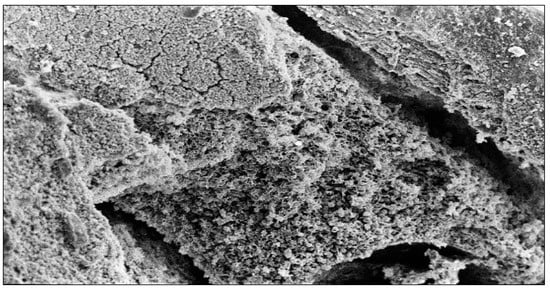

4.1.1. Tooth Samples before Iontophoric Application

4.1.2. SEM Images with Only Ionic Gel